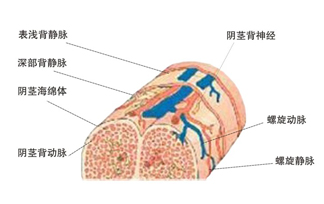

防早泄喷剂作用是舒缓龟头上最敏感的细微神经反应,降低末梢神经敏感性,从而在性交时提高射精阈值,使皮下神经延缓向大脑传送射精命令,从而达到延时的目的。

性生活时间短从根本上说是射精反射所需要的刺激阈值太低,延迟性生活就是提高射精刺激阈值,增加男性生殖器(主要是龟头部位,龟头部位神经末梢最丰富)对性刺激的耐受性。

射精是受大脑神经中枢调节的一种反射,早泄多半是由于大脑皮层抑制过程减弱和男性生殖器过度敏感。高级性中枢兴奋性过高,对脊髓初级射精中枢的抑制过程减弱,以及骶髓射精中枢兴奋性过高所引起。射精并非一定要性交才能引起,包括精神过分紧张、过分激动在内的任何外界刺激都可引起射精。早泄患者往往稍有性刺激就会发生强烈反应,并且马上进入临界状态,结果很快发生射精。